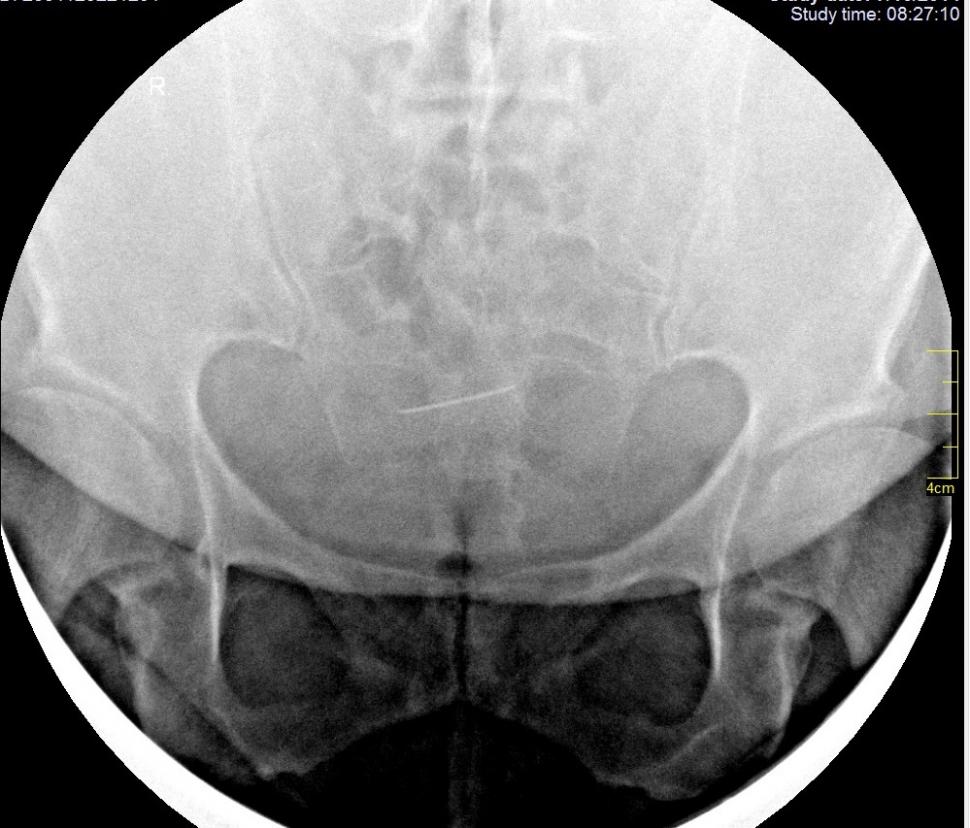

Femeia din Iași se simțea rău și s-a dus la medic. Specialistul a încremenit când a văzut ce apare pe radiografie. „Dumnezeule, e de 30 de ani acolo!” (FOTO)